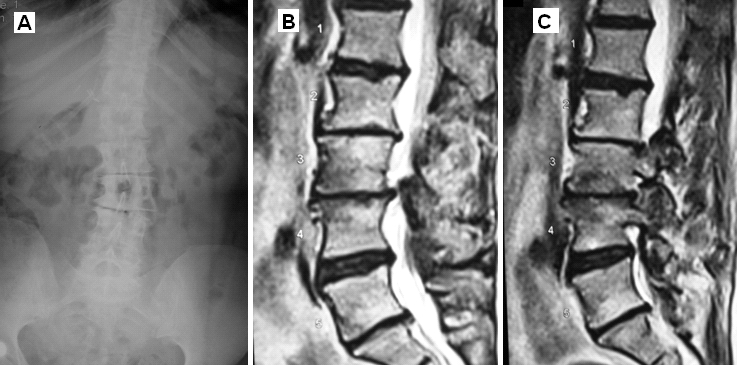

ediyordu. Nörolojik muayenesi normaldi. Hastanın direkt

grafileri ve Manyetik Rezonans Görüntülemesinde lomber

bölgede hemen tüm disk

mesafelerde disk yüksekliğinin azalması, bulging ve nöral foramenlerde

ılımlı daralmalarla giden yaygın spondiloz bulguları ve hafif bir

skolyoz

görülüyordu.

(Direkt

grafi ve MRG incelemelerinde lomber bölgede yaygın spondilotik

değişiklikler, skolyoz ve özellikle L2-L4 arası intervertebral

foramenlerde daralma görülmektedir).